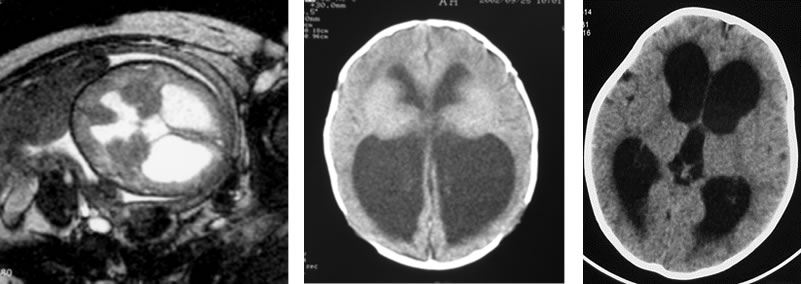

(6)シャント後の脳の変化

赤ちゃんの脳はすばらしい回復力(元に戻る力、可塑性)を持っています。生まれたときに脳の中に水が貯まって脳室が大きくなっていても、シャント手術により脳が発達してその厚みを取り戻すこともまれではありません。一方、シャント手術までの期間や、シャント手術の年齢によっては脳室が縮小しないこともあるので、評価には慎重な神経学的検査や発達検査が必要です。

B:5ヶ月には、徐々に脳の厚みが増しています。白い点はシャントチューブ先端です

C:1才2ヶ月には脳の厚みがまして脳室は縮小してきています

D:2才にはさらに脳の厚みが増して脳室は縮小しています(スリット状脳室)

*細隙脳室(スリット状脳室)

シャント手術後に脳室が縮小しますが、髄液が流れ出てしまって脳室の大きさが正常より小さくなり、CTでは脳室の髄液が描出されないスリット状になることがあります。

脳室が小さくなりすぎると、脳室チューブの先端が詰まって髄液が流れにくくなることがあるので注意を要します。また、脳室がスリット状になるためにシャンと機能不全の症状を繰り返す「スリット状脳室症候群」という複雑な病態があります。